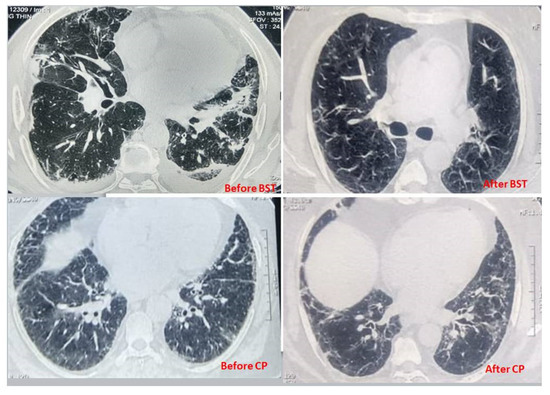

3.6. Computer-Assisted Tomography (CT)

| CT Scan Findings, n (%) | BST Arm (n = 363) | CP Arm (n = 32) | p Value |

| Ground glass opacity | 234 (64.46%) | 18 (56.25%) | 0.15 |

| Local patchy shadows | 145 (39.94%) | 11 (34.37%) | 0.35 |

| B/L patchy shadows | 108 (29.75%) | 9 (28.12%) | 0.89 |

| Interstitial abnormalities | 167 (46%) | 12 (37%) | 0.03 |

| Pulmonary consolidation | 109 (30%) | 7 (21.8%) | 0.09 |

| Pleural effusion | 214 (58.95) | 17 (53.12) | 0.45 |